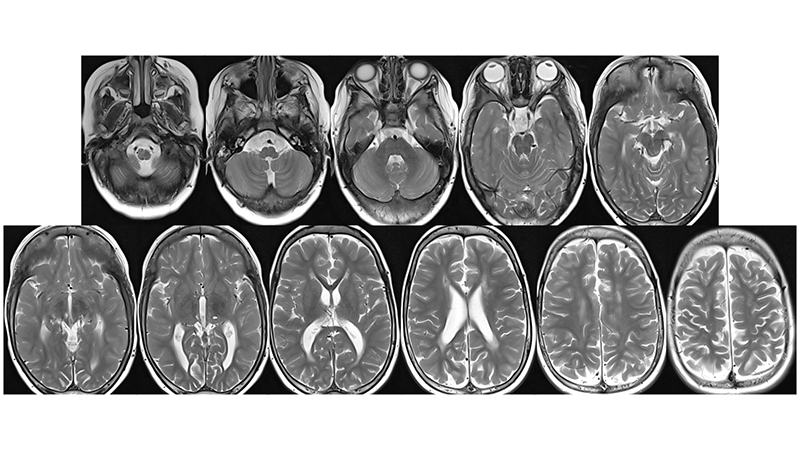

- Στην μαγνητική τομογραφία βλέπουμε μικροισχαιμικές αλλοιώσεις στο εγκεφαλικό στέλεχος και υποεπενδυματικά,

- και υποσκληρίδια αιματώματα αμφοτερόπλευρα, κυρίως δεξιά.

- Στην μαγνητική αγγειογραφία βλέπουμε υποσκληρίδιο αιμάτωμα στο δρέπανο

- και οπισθιοπλάγιους τροφοφόρους κλάδους από τις οπίσθιες εγκεφαλικές αρτηρίες.

- Πρόσφατη μαγνητική τομογραφία δείχνει αναστροφή των ισχαιμικών αλλοιώσεων του εγκεφαλικού στελέχους, αποκατάσταση του κοιλιακού συστήματος με ήπια υποεπενδυματική και φοιώδη ατροφία και πλήρη εξάλειψη των υποσκληριδίων συλλογών.